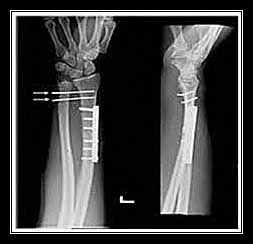

- Kiểm tra X-quang

Đạt kết quả tốt nếu: trên phim thẳng mỏm châm quay, nằm thấp hơn mỏm châm trụ chừng lem. Đường thẳng đi qua 2 mỏm châm quay-trụ tạo với đường ngang chân trời một góc 30°, trên phim nghiêng thấy diện khớp đầu dưới xương quay, nhìn hơi nghiêng 10 -15°, ra trước về phía gan tay.